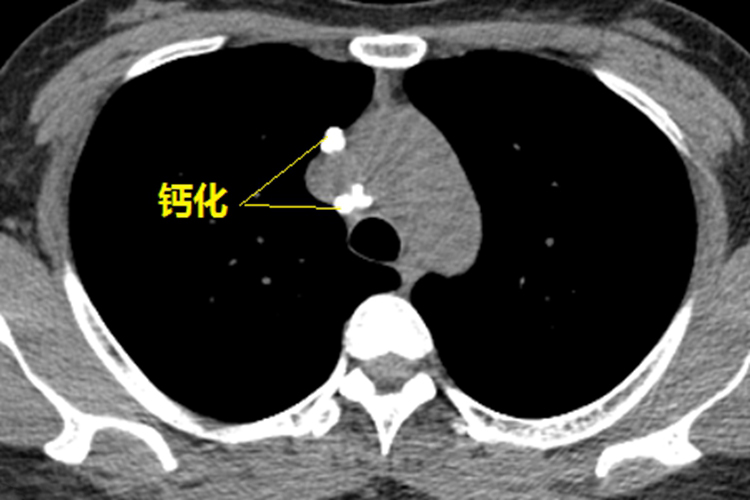

肺部钙化灶

肺部钙化灶表现为高密度阴影,边缘锐利,大小不一,可为斑点状、块状,或球状,呈局限性或弥漫性。

肺部钙化灶常见于肺结核、尘肺、肺结石、肺炎等疾病。肺钙化灶在一般情况下对身体并没有太大的影响,可无须治疗。